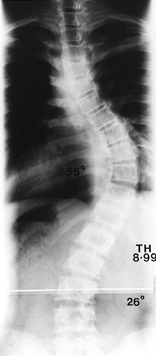

treated with a technique different from that used for thoracic

as for the type II to IV curve patterns. (Fig. 156.25, Fig. 156.26, Fig. 156.27, Fig. 156.28, Fig. 156.29 and Fig. 156.30 show typical cases.)

Figure 156.25. Preoperative AP radiograph of the right thoracic curve.

Figure 156.26. Postoperative AP radiograph of the right thoracic curve.

Figure 156.27. Postoperative lateral radiograph of the right thoracic curve.

Figure 156.28. Preoperative AP radiograph of type I thoracic and lumbar curves.

Figure 156.29. Postoperative lateral radiograph of type I thoracic and lumbar curves.

Figure 156.30. Postoperative AP radiograph of type I thoracic and lumbar curves.s